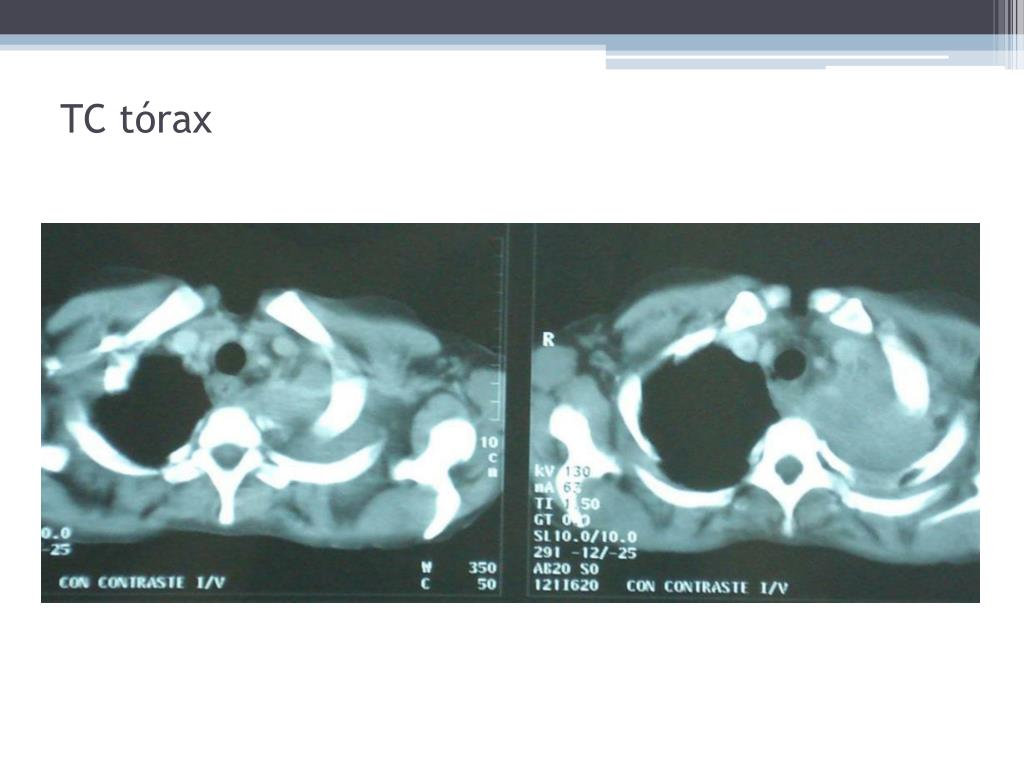

15. TC tórax

21. Síndrome de Pancoast - Diagnóstico • Anamnese e exame físico • RX de tórax demonstra um tumor apical, (em alguns casos, pode ser negativa e o tumor identificado apenas na TAC do tórax. • RNM é útil para melhor avaliação da invasão tumoral através da pleura, do envolvimento do plexo braquial e dos vasos subclávios. • Broncoscopia e citologia são conclusivas em 10 a 20%. • O método diagnóstico mais eficaz é a punção transtorácica percutânea guiada por USG ou TC